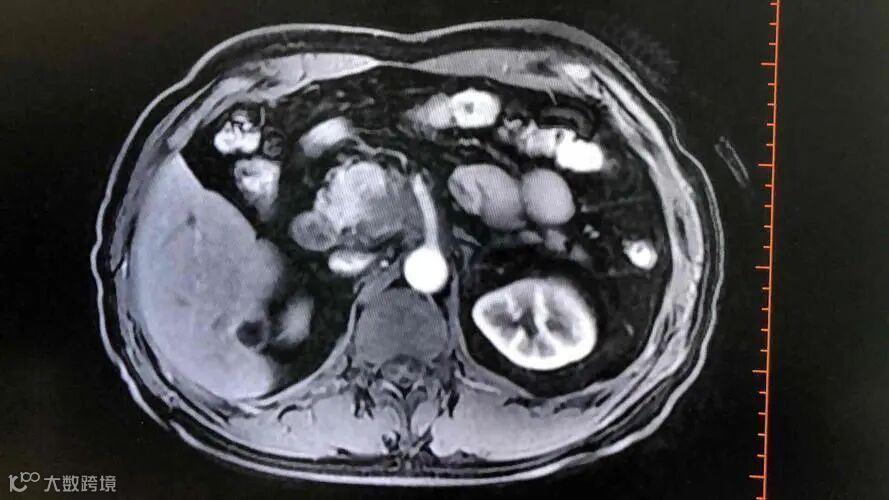

胰腺癌的隐匿性,不仅让症状模糊,也让检查难度加大。普通B超常因肠气干扰,难以清晰显示胰腺结构。

增强CT和磁共振成像目前是诊断早期胰腺癌的主要手段。2023年《中华消化杂志》一项分析指出,增强CT对胰腺癌的敏感性为约89%,远高于常规检查。